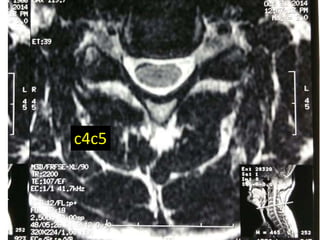

c4c5

Mid-sagittal diameter: width

1:5 ratio leads to necrosis of gray

matter